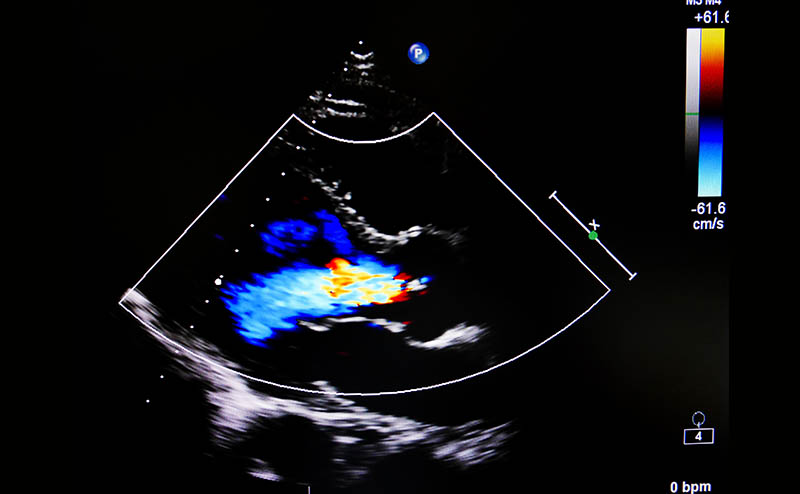

Color Flow Doppler (CFD) evaluation can then be performed, and is the most essential component of the valvular assessment. CFD can not only diagnose MR by discovering the presence of a regurgitant jet, but also help in determining its mechanism, severity, and hemodynamic impact. Once a regurgitant jet is identified, evaluate the jet’s three main components and direction of flow. Jet direction consists of three categories: central, eccentric, and multiple jets. In the presence of a flail leaflet, the regurgitant jet is typically located opposite to the affected leaflet (anterior flail leaflet = posterolateral jet, posterior flail leaflet = anteromedial jet). Presence of an eccentric jet should be considered severe until proven otherwise, and should alert you to the possibility of structural abnormalities.2 Multiple jets in unpredictable directions are often seen in patients with endocarditis.

The patient continued to demonstrate symptoms and vitals consistent with shock. Given concern for fluid overload without clear etiology, further investigation was done with point-of-care cardiac ultrasound by a more experienced practitioner while awaiting comprehensive echocardiography. This showed left atrial dilation but again normal LV size and function. Color flow doppler was applied, showing a posterolateral eccentric MR jet. On acquisition of higher quality images, a flail leaflet could be visualized. Review of further records showed a TTE from ~2 years ago quantifying the patient’s mitral regurgitation as mild. Consultation with cardiology at the time had revealed mitral annular calcification as the suspected etiology.